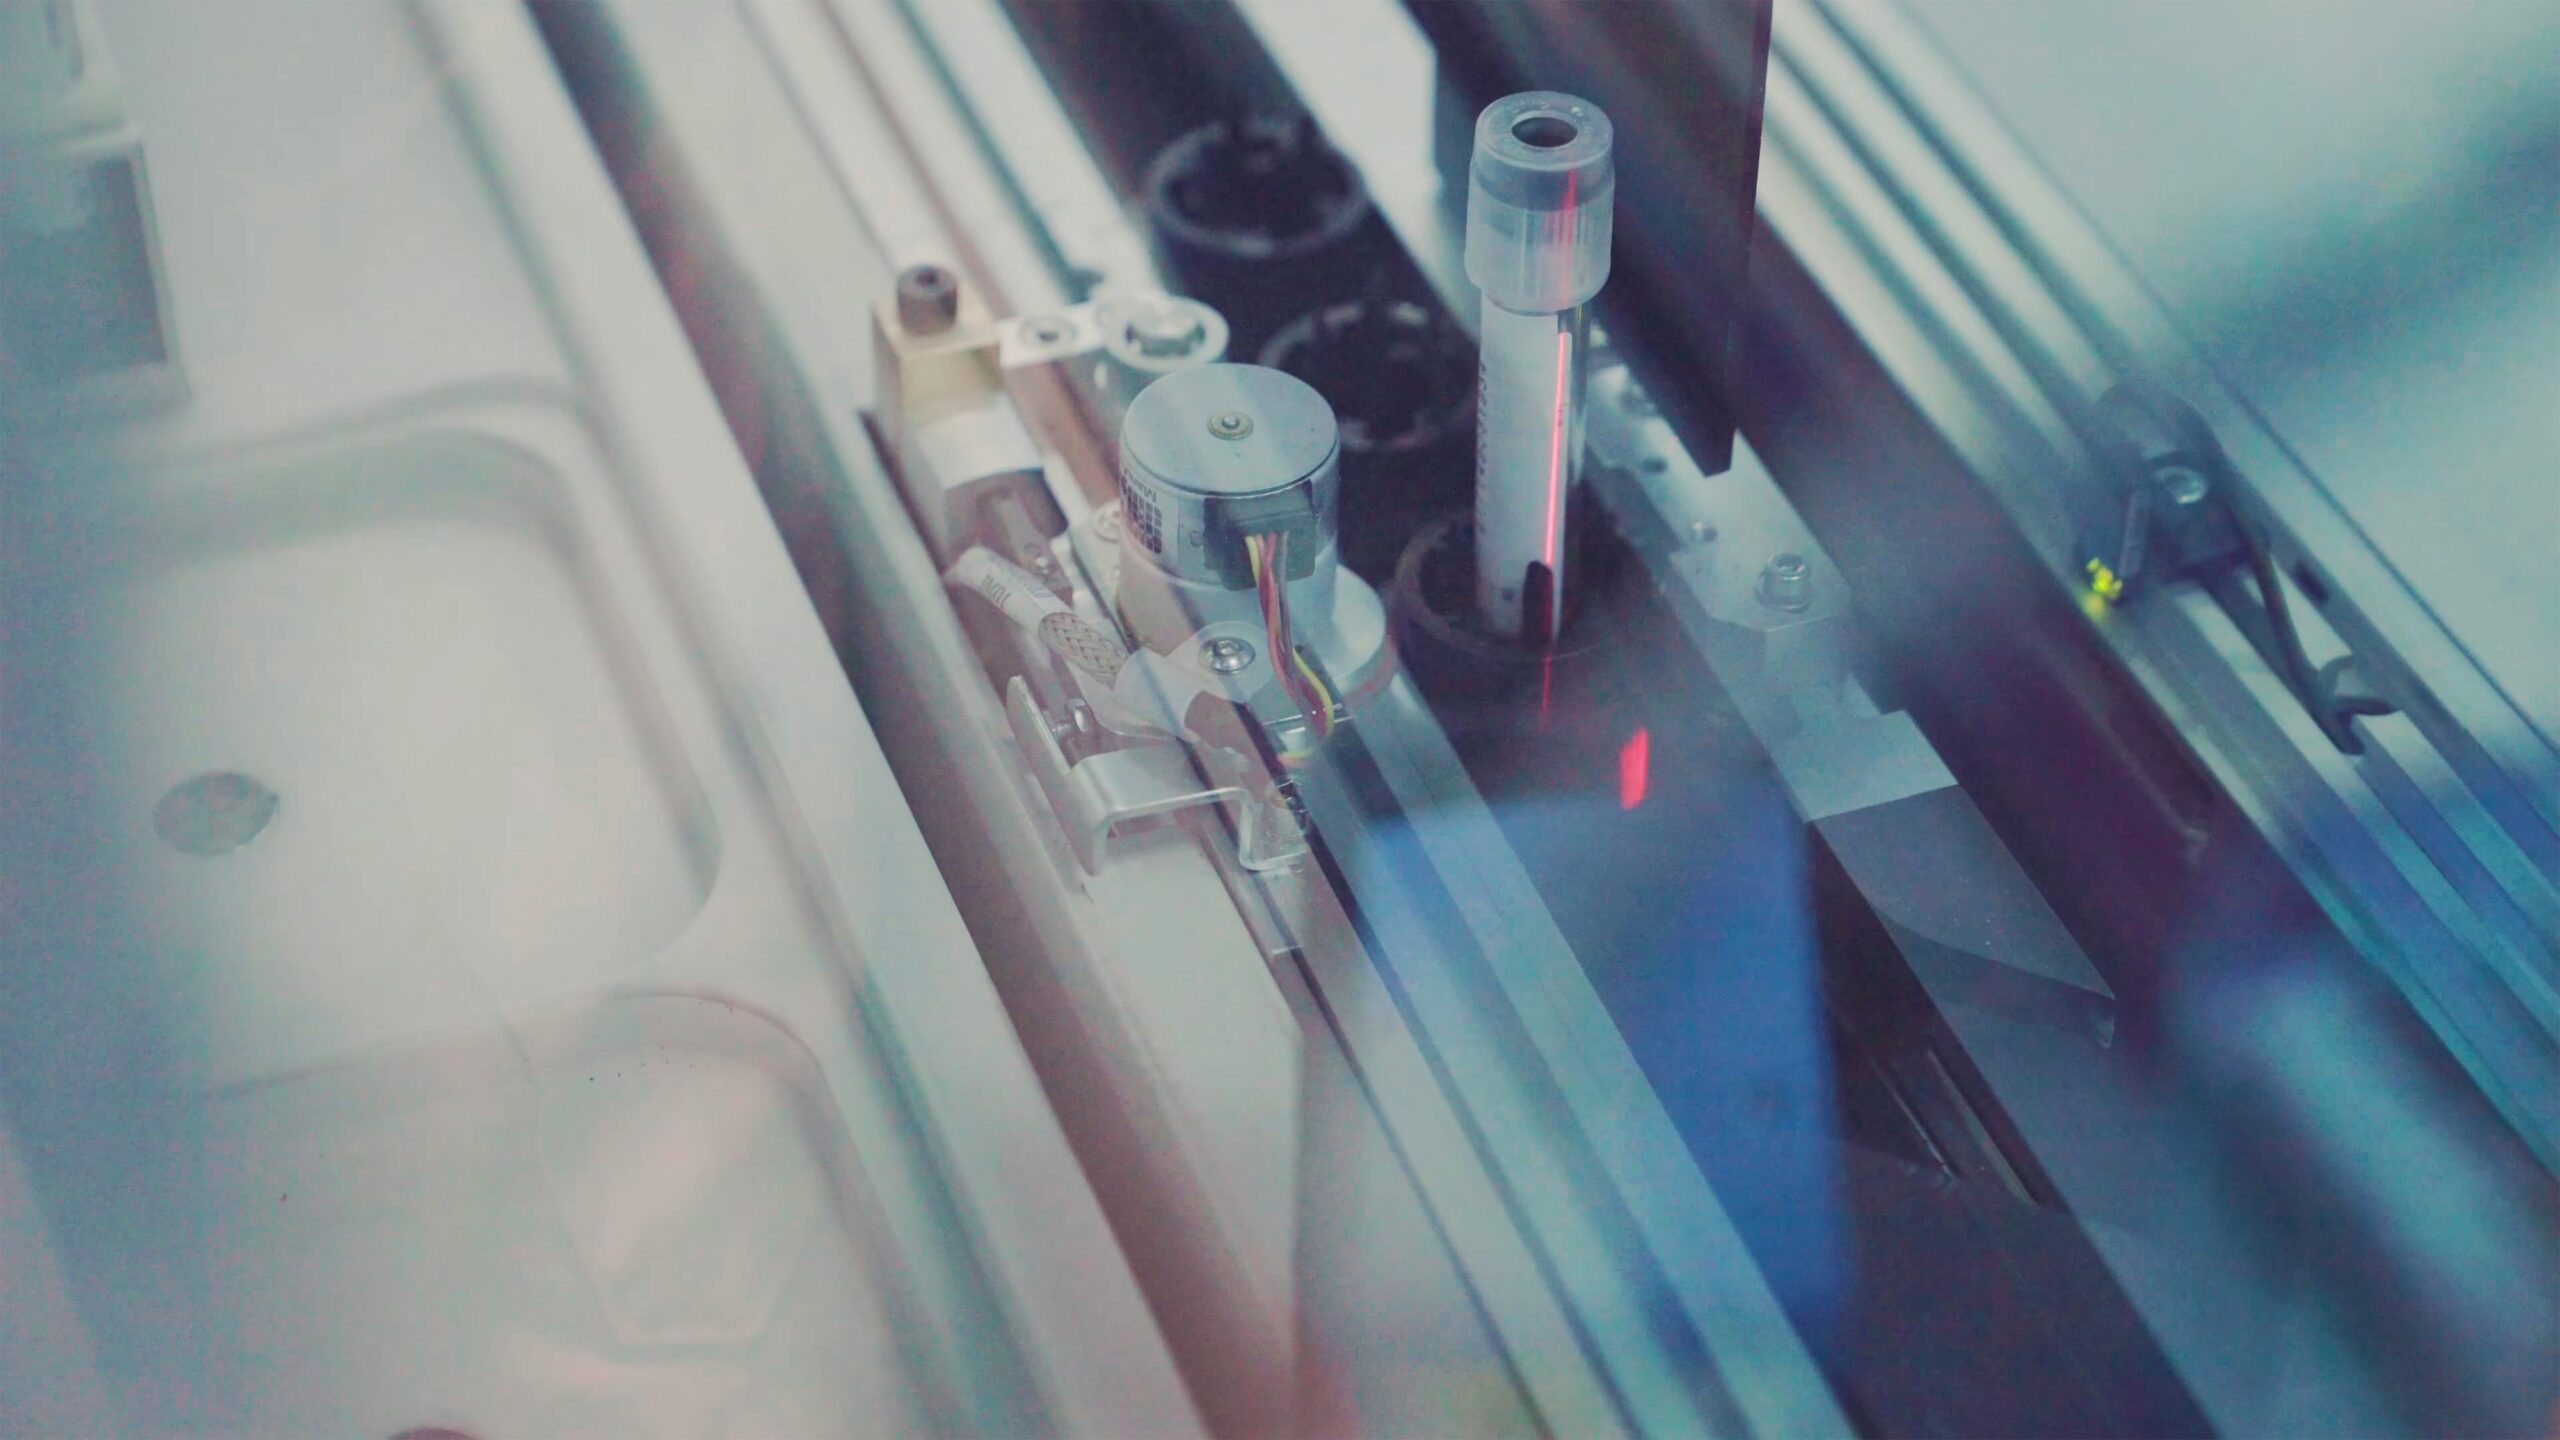

Diagnostyka mikrobiologiczna stanowi fundament w medycynie, przemyśle farmaceutycznym, spożywczym oraz wielu innych sektorach, gdzie precyzja i szybkość analiz mają ogromne znaczenie. Aby sprostać wyzwaniom współczesnego świata, konieczne jest jednak sukcesywne wdrażanie nowoczesnych rozwiązań, takich jak automatyzacja procesów technologicznych. W niniejszym artykule przyjrzymy się temu, dlaczego automatyzacja staje się kluczowym aspektem w diagnostyce mikrobiologicznej i jakie […]